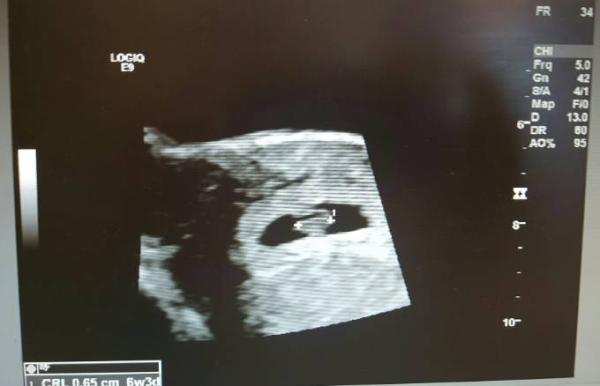

Hallo ihr lieben..hatte nun auch meinen US und der Krümel hat einen Herzschlag von 133. Ich war ja so besorgt da ich rein gar nichts gespürt habe bisher. Wurde zwar zurück datiert auf 6+3...aber hauptsache alles gut. ET ist nun der 22.07

Bild zu Glücklich - Forum für Juli - Mamis